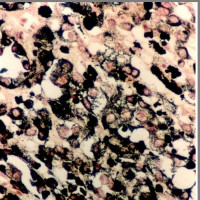

メラノーシスの部分の組織所見です。核の異型性がなくメラニン色素顆粒がみられます。脳底部や小脳の実質内には,散在性にメラニン顆粒を豊富に含む多数の迷入細胞が認められます。くも膜下腔を埋め尽くしたり,軟膜血管に沿って脳の深部に入り込んだり,軟膜から直接脳組織に浸潤したりしています。しかし,脳実質組織構造の乱れはなく,神経機能も侵されないために,局所神経症候を呈することは少ないです。